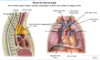

What structures are shown?

Explain what you can see from posterior- middle- anterior

Explain what is seen inferiorly

What is the ligamentous connection between the inferior most structure and middle structure?

Most posterior structure- trachea, bifurcation into L and R main bronchi.

Most anterior is the superior vena cava, receiving the R and L brachiocephalic veins. The R and L brachiocephalic veins receive from the R and L internal jugular vein.

Middle structure - Arch of aorta, on R side brachiocephalic trunk which splits into the R subclavian and R common carotid. Splits into the L internal carotid and L subclavian.

Inferior stucture is the pulmonary trunk.

Ligamentous connection between the aorta and pulmonary trunk is called the ductus arteriosus. It fuses soon after birth- open in utero to bypass the deoxygenated blood past the lungs and straight into the aorta.

What happens if the ductus arteriosis remains open?

If the ductus arteriosus remains open this is called a patent ductus arteriosus and leads to mixing of deoxygenated blood and oxygenated blood.

This can put a strain on the heart and increase blood pressure in lung arteries.